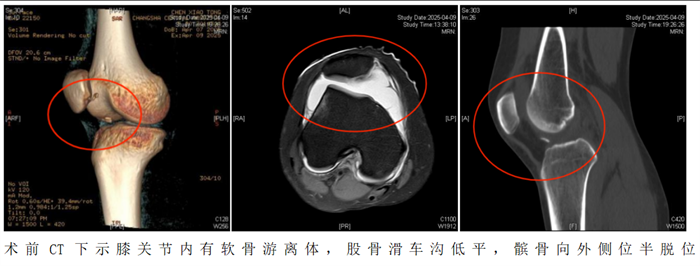

20岁的陈静怡(化名)在打篮球跳跃落地时,不幸发生右膝盖骨脱位。虽然后来自行复位,但随即出现右膝疼痛、肿胀及关节活动受限。经立博体育 检查诊断为“急性髌骨脱位,髌骨内侧、股骨外侧髁撕脱骨折”。通过微创手术,成功将“脱轨”的髌骨复位到“轨道”上。

“患者入院后,我们为她制定了周密的个性化治疗方案,采用‘关节镜下髌骨成形术+纽扣十字缝合法软骨修复术’帮助恢复膝关节功能。”据立博体育|实时赛事直播与比分|权威专家分析与体育竞猜平台

运动医学、创伤关节、骨病科主任丑克介绍,这项联合术式在省内少见,因患者游离软骨骨碎片大,软骨下骨骨质有血运,髌骨内下缘软骨缺损面积大,通过高强度缝线采用纽扣十字缝合法原位缝合剥脱的软骨块成形髌骨,犹如为膝关节打造了一个防护网。手术过程顺利,术后患者恢复良好。

2.如果出现以下情况需要考虑手术治疗。初次脱位后出现髌骨或股骨软骨骨折导致关节内出现游离体时,必须手术治疗。关节镜是目前成熟的关节内镜技术,医生通过内镜,直视下观察髌骨的损伤,取出游离体并修复软骨,行内侧支持带紧缩和外侧支持带松解术,即可取得满意的疗效。该手术是微创手术操作,创伤小,恢复快,多数患者术后第1天即可下地活动。